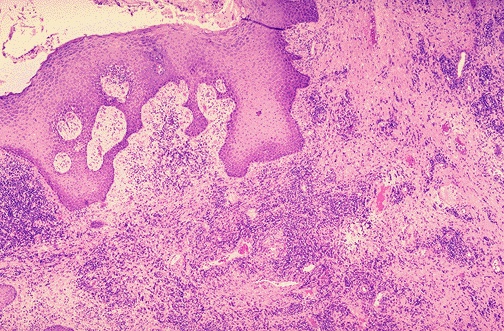

Acne is marked by folliculitis, and the inflammation can spread to involve the surrounding dermis, as seen here at low magnification.